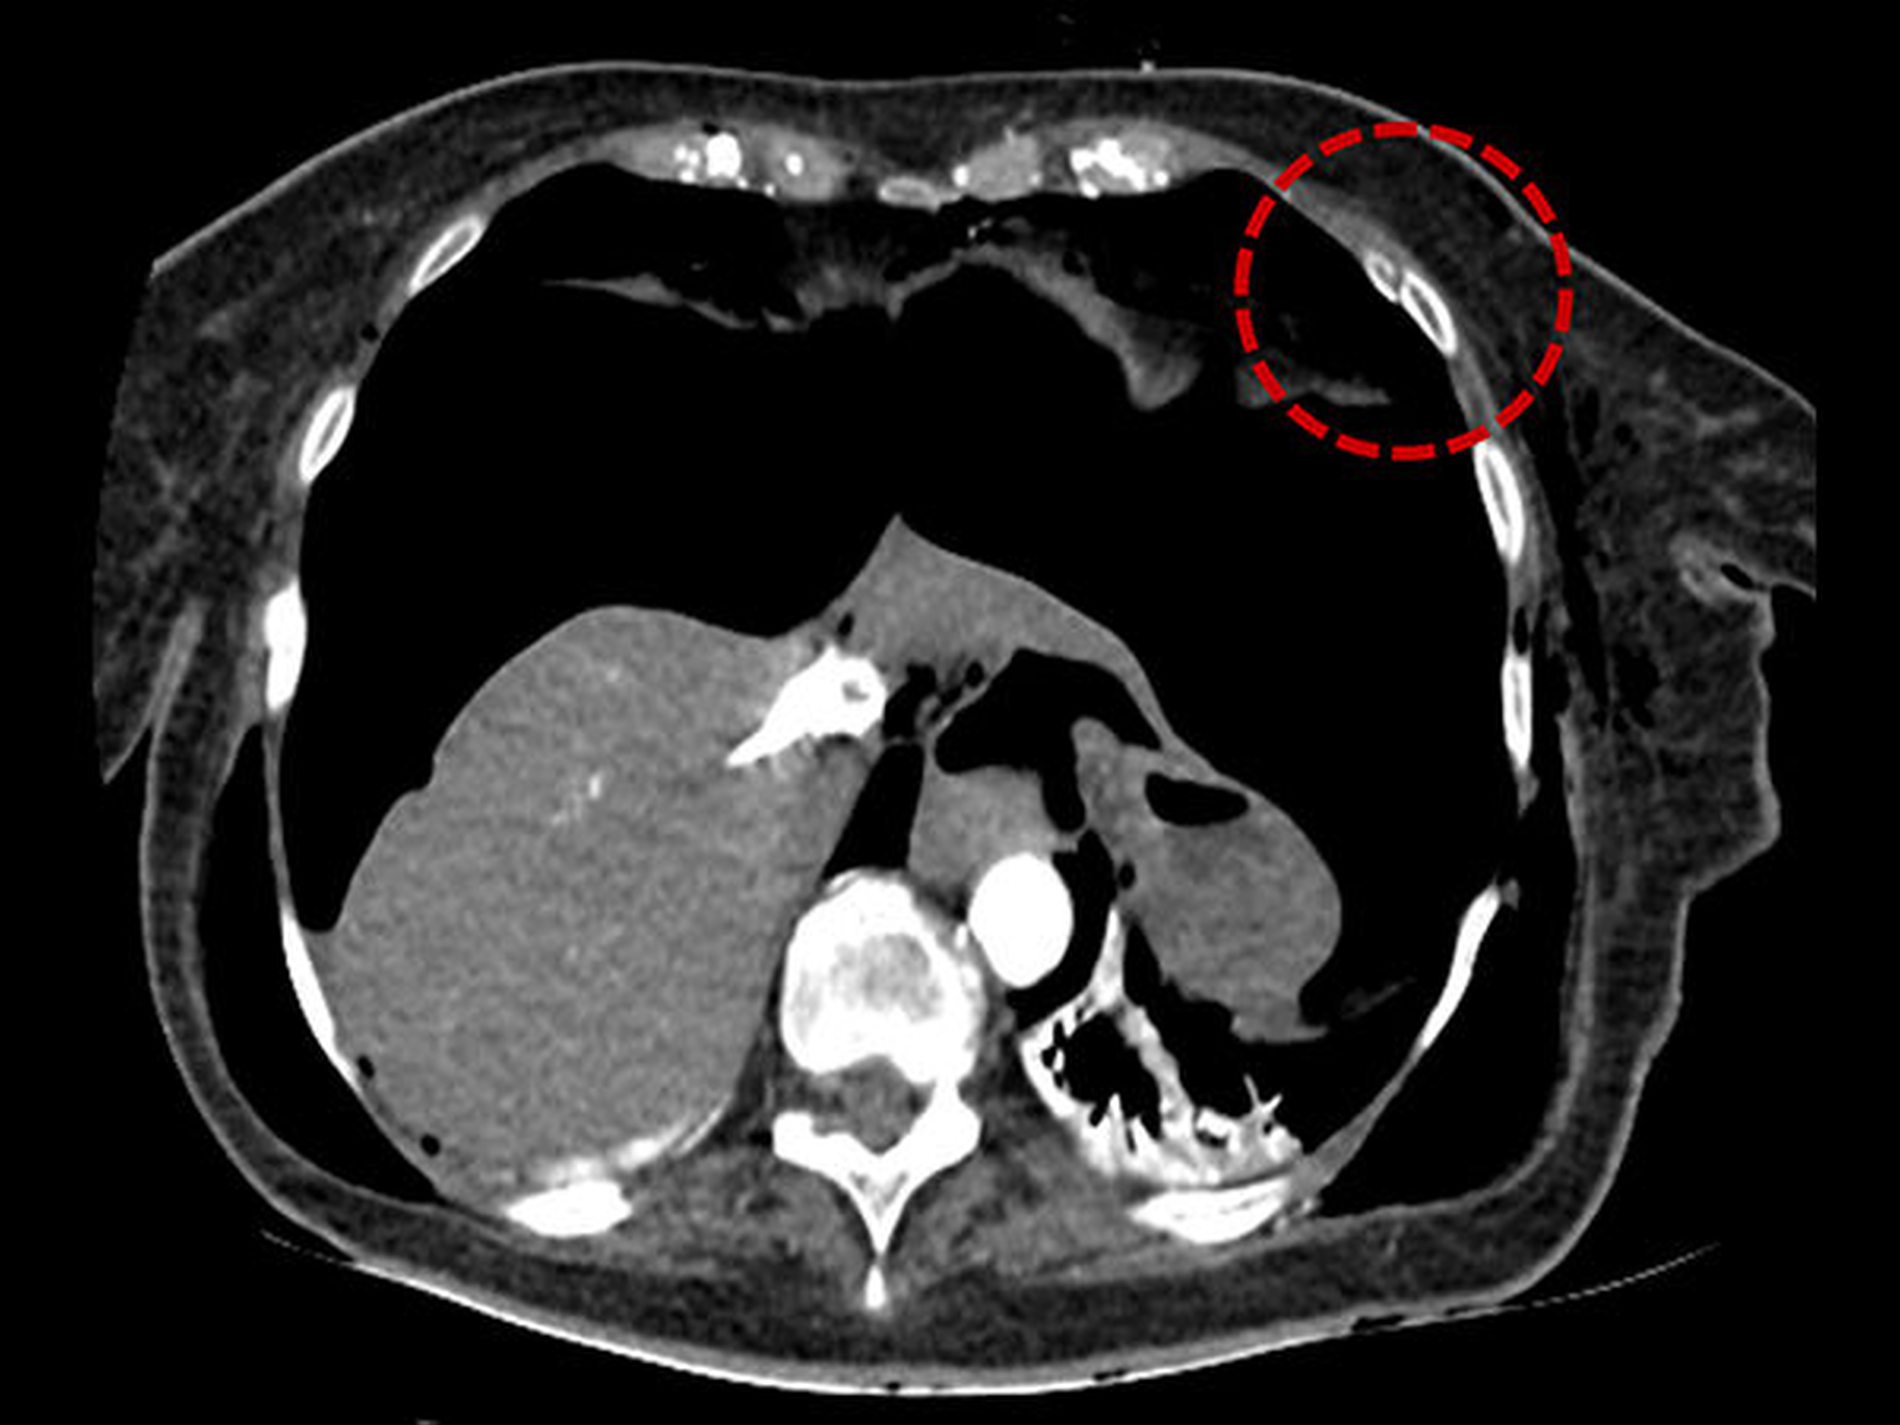

Im Rahmen der sofort eingeleiteten kardio-pulmonalen Reanimation erfolgte die unmittelbare Reintubation der Patientin, die einen schnellen ROSC (return of spontan circulation) zur Folge hatte. Im Zuge der durchgeführten Reanimationsmaßnahmen und der vorbestehenden Osteoporose kam es zu einer linksseitigen Rippenserienfraktur der Costae 3-7 (Abbildung 1), die einen beidseitigen Spannungspneumothorax und ein Pneumoperitoneum über eine Zwerchfellleckage nach sich führte.

Der Spannungspneumothorax wurde akut per Nadeldekompressionen und dann über Thoraxdrainagen beidseits entlastet. In der anschließend durchgeführten CT-Untersuchung von Thorax und Abdomen zeigte sich neben dem beidseitigen, entlasteten Mantelpneumothorax zusätzlich ein Pneumomediastinum mit Luftansammlungen im oberen, ventralen und dorsalen Mediastinum (Abbildung 2), zusätzlich dazu eine Ansammlung von freier Luft im Abdomen (Abbildung 3).